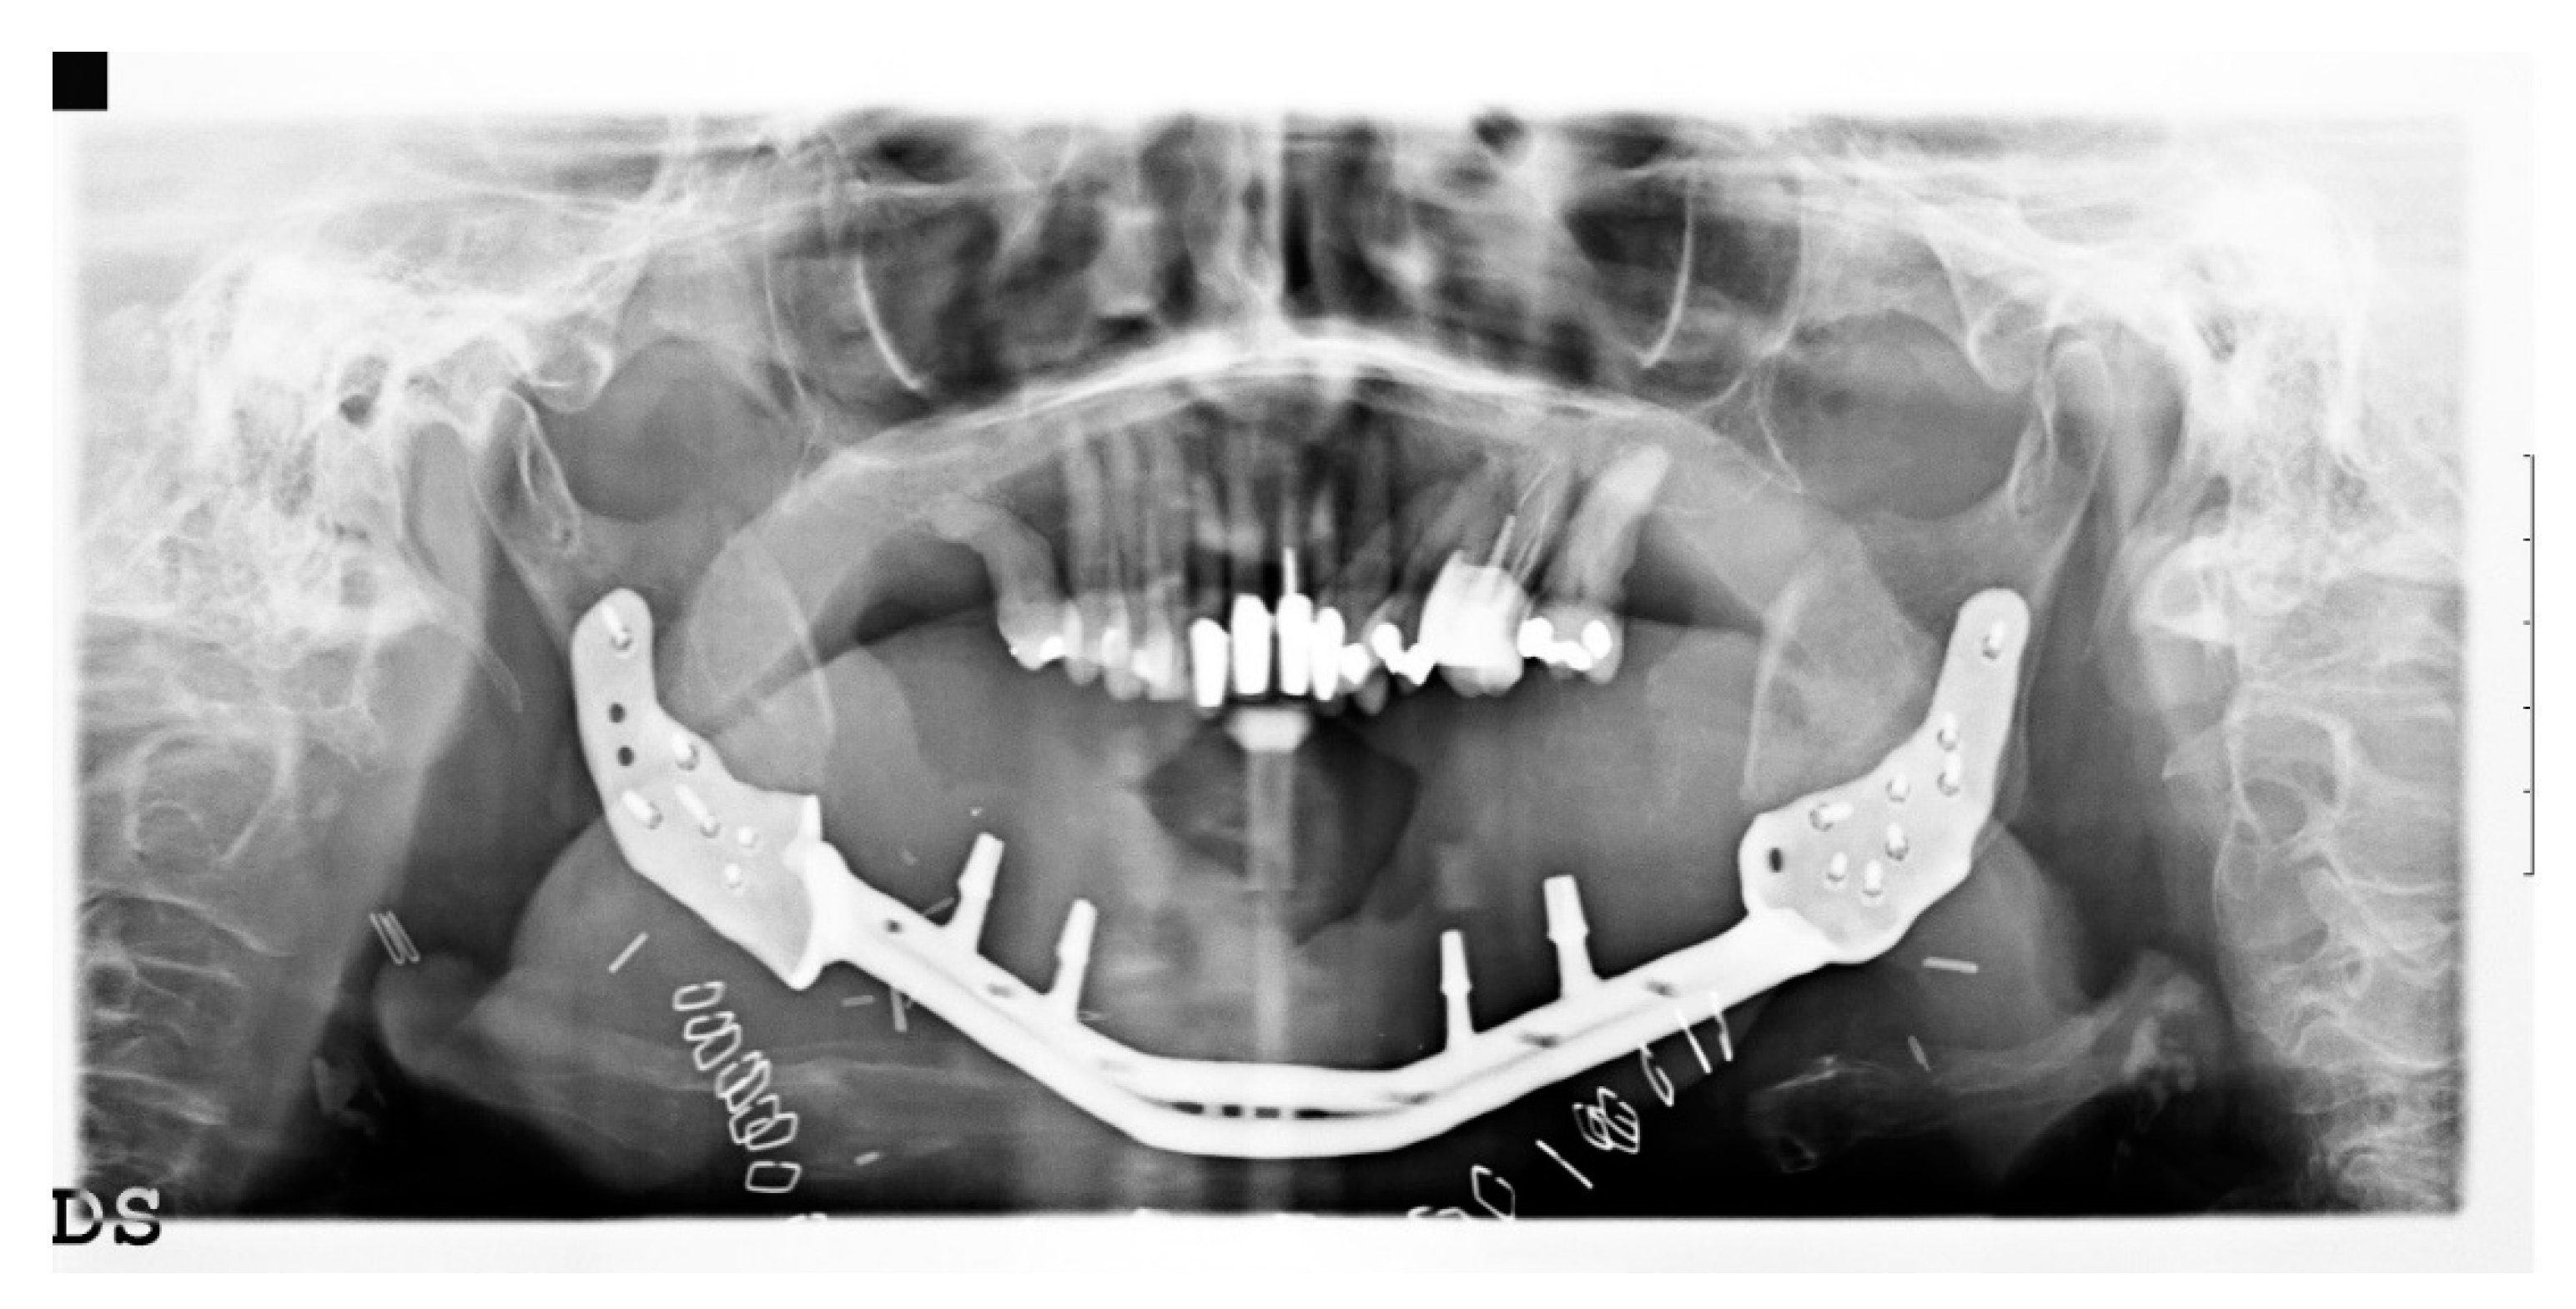

2. Case Presentation

2.5. Surgery

- The jaw prosthesis placement and fixation was completed using screws (Tekka®, Pesaro, Italy) of 2 mm Ø and 7 to 9 mm length to attach them to the mandibular ramus.